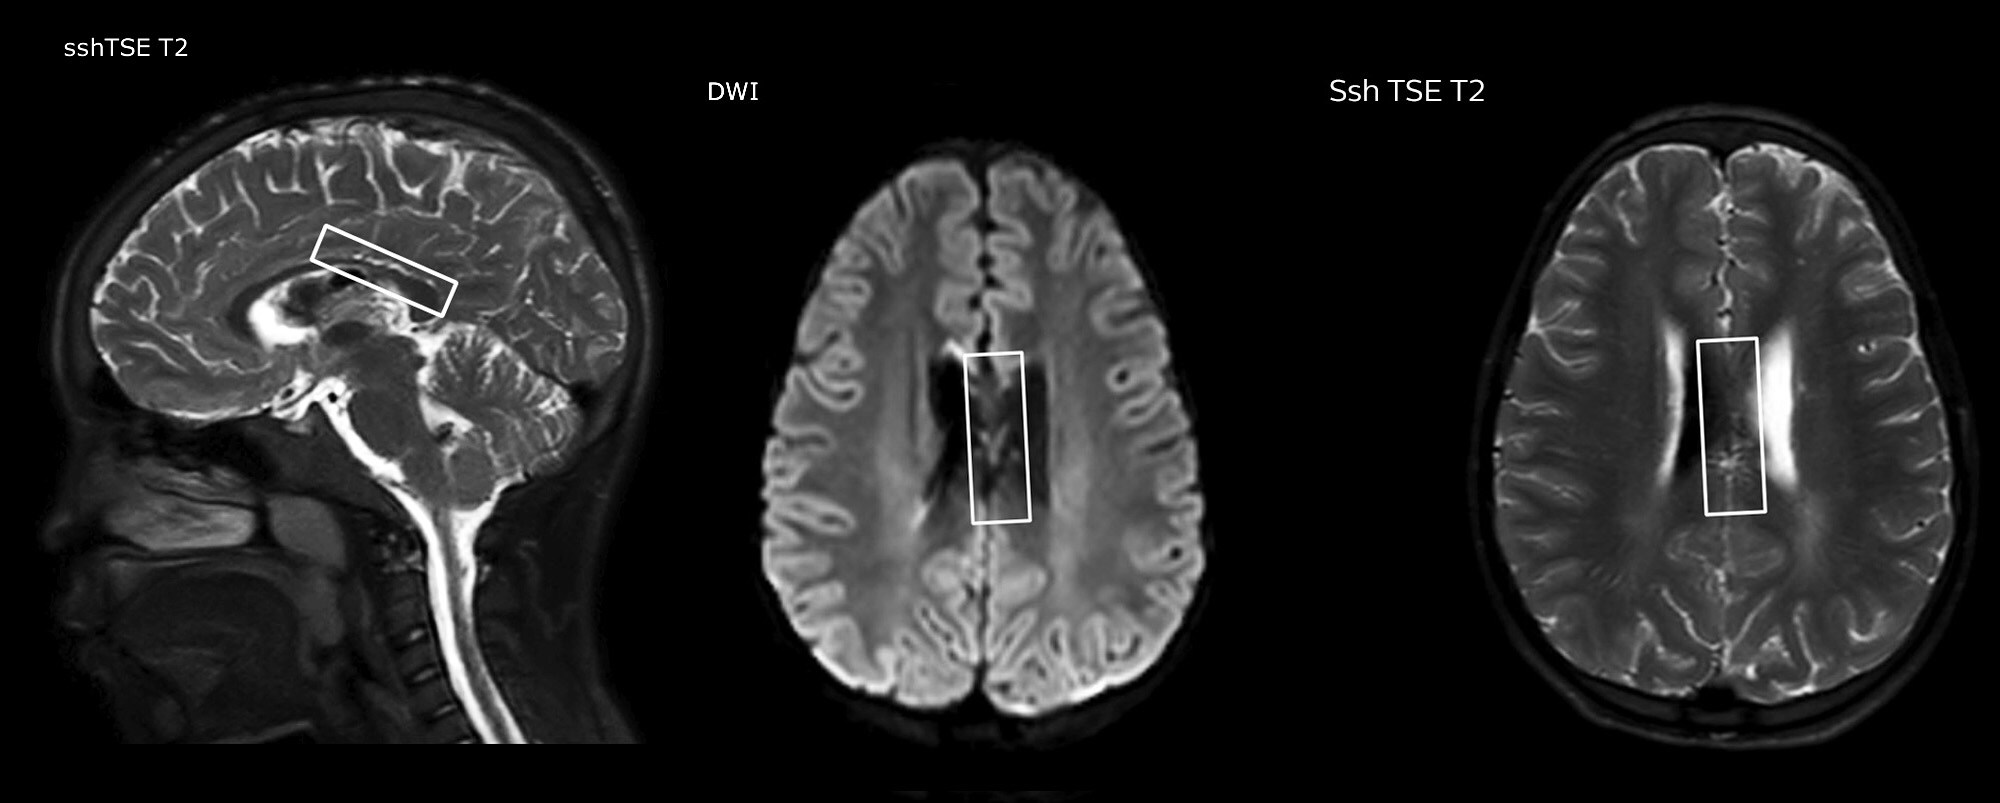

“In combination with diffusion weighted imaging, it can help give a more extended assessment of the degree of perfusion abnormality in a patient who is suffering acute ischemia. We have a number of patients who have chronic arterial insufficiency due to prior arterial abnormalities or acquired arterial abnormalities such as sickle cell disease or neurofibromatosis. Sometimes the child’s first manifestation of disease progression is a reduction in brain perfusion before stroke symptoms manifest clinically or in diffusion weighted imaging. We use pCASL to help delineate the perfusion abnormality.”

To other new users I would recommend to also start to interpret the pCASL images in comparison with other standard imaging – T2 and FLAIR and DWI – until the user gains confidence in interpreting these images by themselves.” “A powerful use of pCASL is in patients with chronic cerebrovascular stenosis, where clinicians desire information on how compensatory mechanisms of the brain are performing to enable perfusion to the brain. Often clinicians take into account how the compensatory mechanisms appear to help to provide adequate perfusion to the patient’s brain, and they may intervene surgically or make some other management decision.” “Another special application is the assessment of cerebrovascular reactivity with a Diamox perfusion exam, where we subtract two sets of pCASL images.”